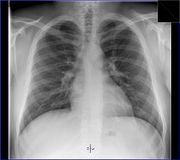

Lékařské využití

Poté, co Röntgen objevil využití pro pozorování kostních struktur, se rozvinulo jeho užívání v lékařském snímkování. Rentgenové záření může být využito pro zobrazení detailů kostí a zubů (skiagrafie), popřípadě za pomoci vhodných technik i ke zkoumání měkké tkáně (denzitografie, subtrakční skiagrafie, tomografie). Radiologie je specializovaný obor lékařství využívající rentgenového záření v diagnostice. Toto je pravděpodobně nejčastější využití rentgenového záření.